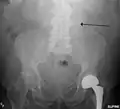

-

A ruptured AAA with an open arrow marking the aneurysm and the closed arrow marking the free blood in the abdomen -

The faint outline of the calcified wall of an AAA as seen on a plain X-ray -